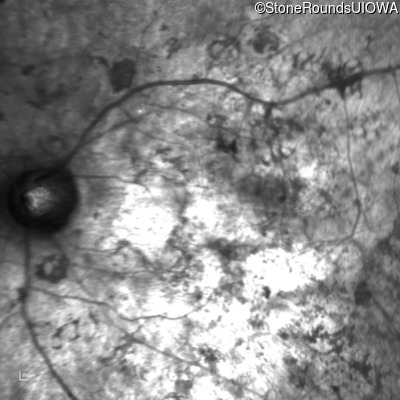

Infrared Fundus Photograph - Left - Hand Motion sc

Exemplar